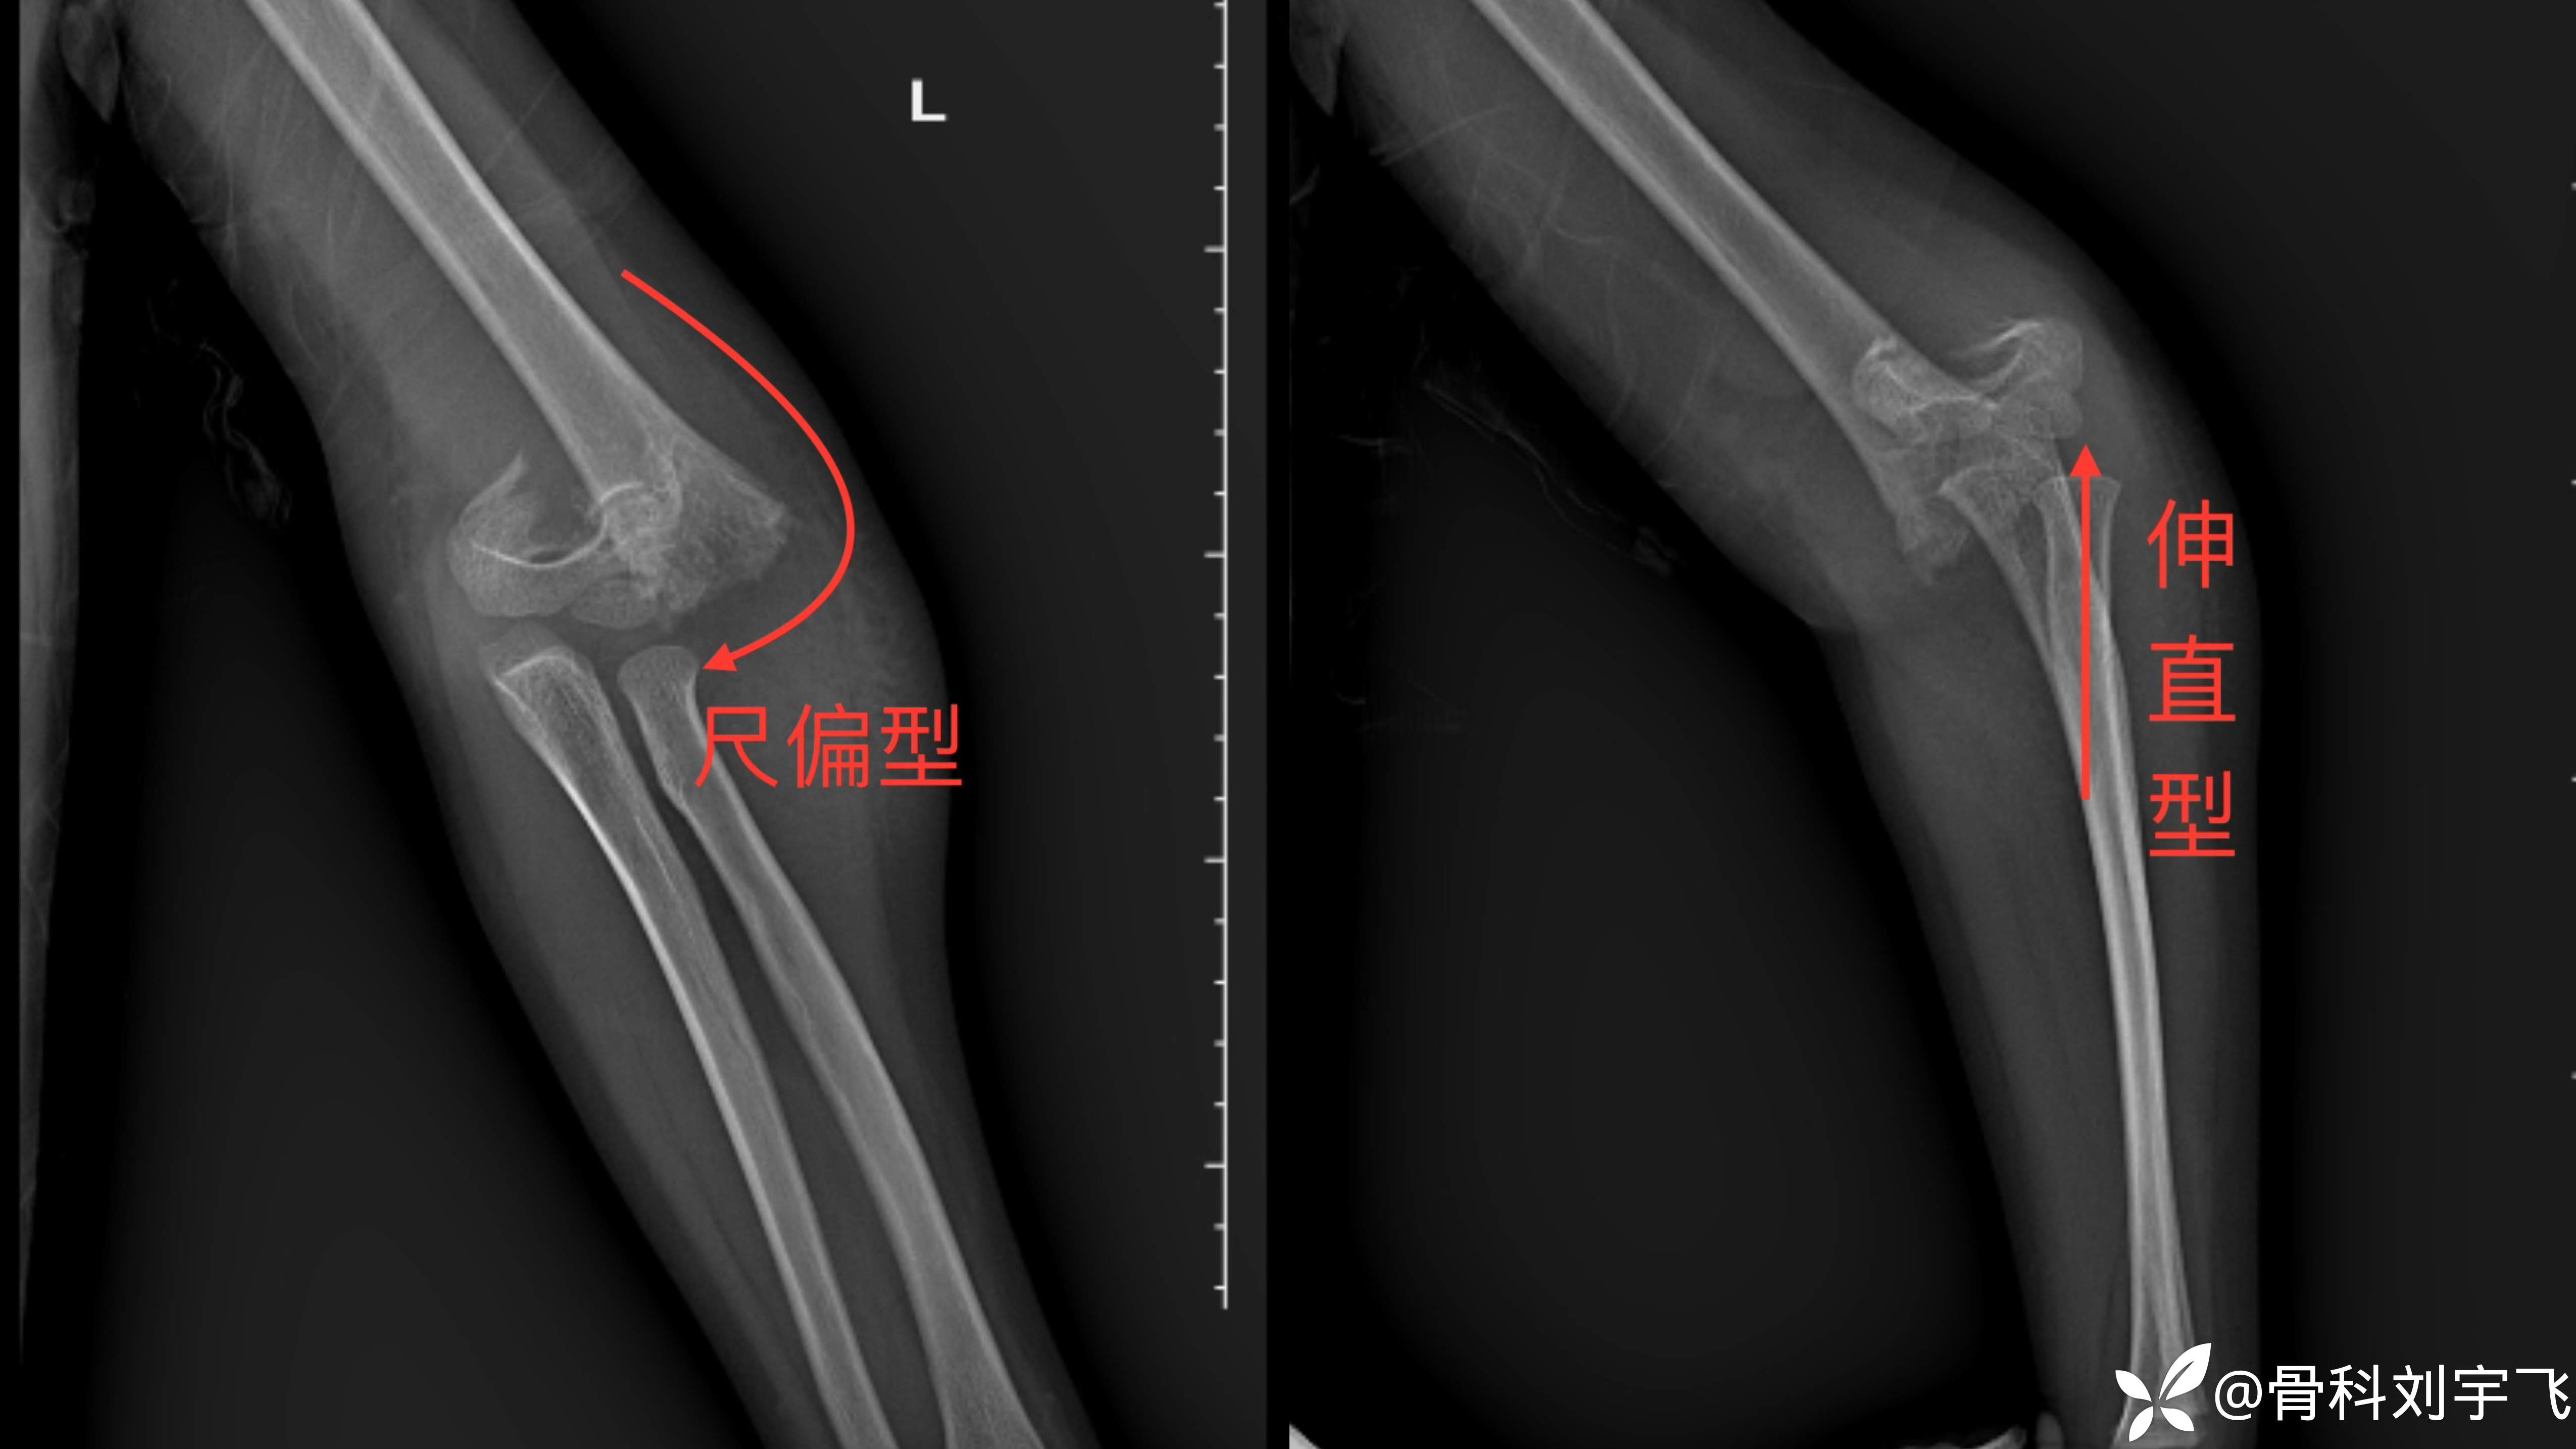

【临床诊断】:肱骨髁上骨折GartlandⅢ型完全移位

【治疗经过及结果】:明确诊断其小儿骨折属于肱骨髁上骨折GartlandⅢ型完全移位针对选择方案有手术治疗、保守治疗两种方案,给予患者家属沟通讲清楚手术及保守治疗的利弊关系后患者家属表示优先保守治疗手法复位,接受复位失败后手术治疗。

首次复位后:

正位尺偏移位恢复,侧位骨折端仍有旋转,石膏固定,择期调整。